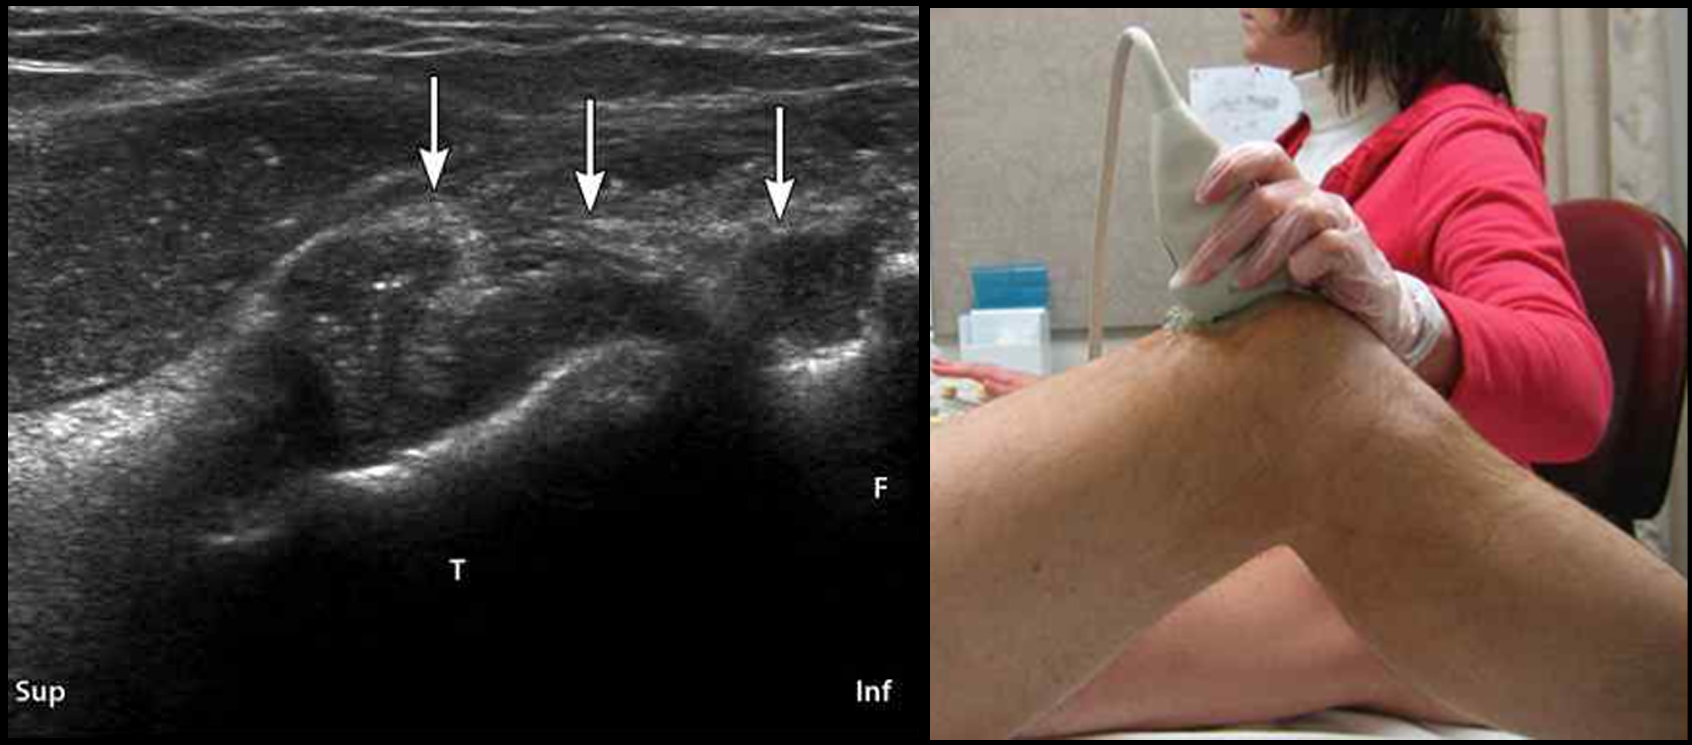

무릎.jpg

■ 포터블 초음파로 진단한 근육·관절·힘줄…근골격계 임상 강점

특히 근육·관절·힘줄·인대 평가에서도 강점을 보인 포터블 초음파는 근육 두께와 섬유 배열, 부종과 섬유화 여부를 실시간으로 확인할 수 있으며, 관절 초음파를 통해 활막 비후, 삼출액, 염증 활성도(Power Doppler)를 객관적으로 평가할 수 있다.

무릎 초음파는 전방·내측·외측·후방 네 영역으로 나눠 체계적으로 접근하며, 권 회장이 제시한 실제 임상 영상에선 활막염에 부합하는 연부조직 증식과 점액낭 비후 소견이 관찰됐다.

권 회장은 아울러 “열악한 환경에서 시행한 Hand-Held 초음파 검사에서도 진단 정확도는 매우 높게 나타났다”며 “포터블 초음파는 방문진료 시대에 한의사의 임상 술기를 한 단계 끌어올리는 도구”라고 강조했다.